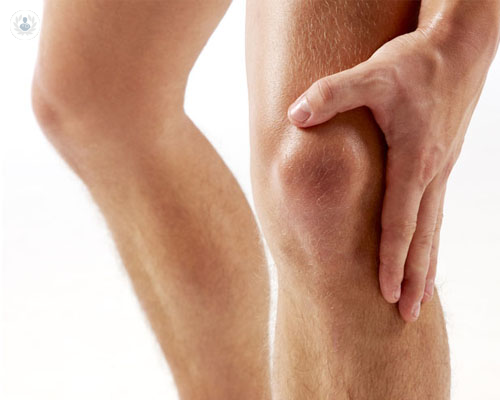

La rodilla es la articulación más afectada por la artrosis

La artrosis es una enfermedad degenerativa que afecta a las articulaciones, sobre todo afectando al desgaste de la rodilla. El Dr. Strauch, experto en Traumatología, habla de la patología y de su tratamiento.